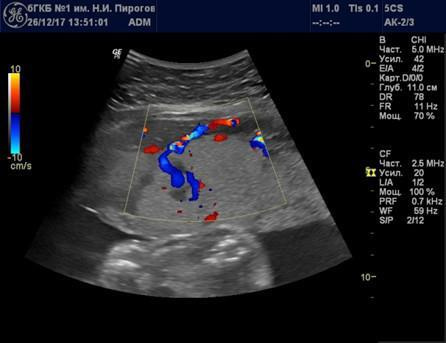

Выявляемые при серошкальном исследовании плаценты ан- или гипоэхогенные зоны чаще всего являются эхографическими срезами участков расширения ее МВП (Рис. 7) и значительно реже сосудов плода (Рис. 8). Расширение МВП может быть связано как с поступлением материнской артериальной крови, и отражать одно из состояний артериального капиллярного русла маточно-плацентарного кровотока (Рис. 9), так и с оттоком в материнское русло венозной крови (Рис. 10). При этом направление тока крови может быть установлено при цветовом допплеровском картировании (ЦДК). Следует иметь в виду, что венозное звено маточно-плацентарного кровообращения состоит из двух функциональных частей: венозных коллекторов плацентарного ложа возле разделительных септ и краевых синусов [10], которые также могут быть расширены (Рис. 11).

Рис. 9. Беременность 24 нед. Расширение межворсинкового пространства, связанное с артериальным притоком, в серошкальном режиме (а) и режиме цветового допплеровского картирования (б).